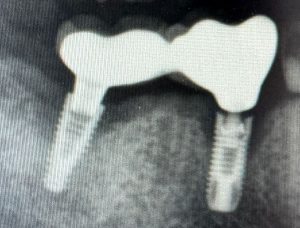

El implante no fracasa en el hueso, fracasa en el entorno

La osteointegración es un proceso multifactorial, regulado por la interacción dinámica entre: • Inflamación controlada• Angiogénesis y perfusión tisular• Respuesta inmune innata• Remodelado óseo continuo•

Impacto del Déficit Nutricional en el Fracaso Temprano de Implantes

1. Vitamina D y fracaso de implantes Estudios clínicos han demostrado que pacientes con niveles bajos de vitamina D (<20 ng/ml) tienen hasta 3 veces